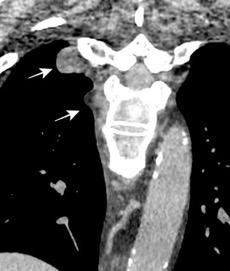

Hematoma pleural después de cateterismo.

Rotura de aneurisma de arteria subclavia Aneurisma “deshinchado” Hemotórax

Fallece en el acto de tomar esta radiografía. La mayoría ateroescleróticos. Más frecuente a la derecha.La rotura: 32-47% de las muertes.

Sun J et al. Isolated True Subclavian Aneurysm without Aberrant Subclavian Artery or Coarctation of Descending Aorta. Annals of Vascular Surgery 2021